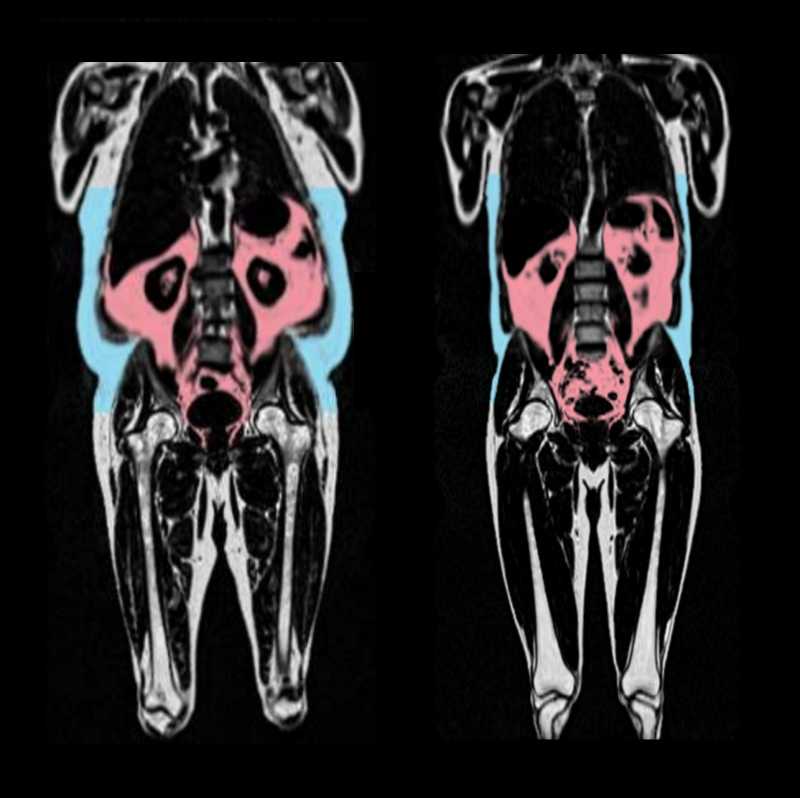

Распределение жира в организме исследуется с помощью МРТ-сканирования

МРТ-изображения участников. Слева — человек с бо́льшим количеством висцерального жира (красный) и подкожного жира (синий). Credit: AMRA Medical |

Ученые предположили, что на скорость старения сердца влияют распределение жира в организме и фенотип жировой ткани, то есть количество висцерального жира (скрытого жира, окружающего внутренние органы) и абдоминального подкожного жира, расположенного в области живота, а также тип распределения жировой ткани. (Андроидное накопление жира, в области живота и верхней части тела, формирует фигуру типа «яблоко», гиноидное, в области ягодиц и бедер, — фигуру типа «груша», более характерную для женщин).